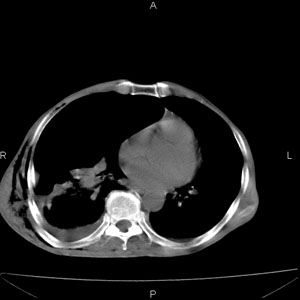

患者男,77岁,于3日前从树上摔下,头部查ct示蛛血,硬膜下出血,上腹部ct未见明显异常,右侧胸腔积液,左侧如常。肺部拍片示右侧肋骨多发骨折住院后今日来查肺部ct,我看到的是1。右侧胸腔血气胸并右肺上叶,中叶压缩性肺不张,2。右肺下叶肺挫伤并多发肋骨骨折,肌内及皮下积气3。左侧少量胸腔积液,我想请教的是3天前左侧胸腔里没有积液今天怎么出现了呢,是什么原因呢?请讨论。

回复楼主   左侧液气胸,液体来源1、肯定有血液成分,多少不一定。2、胸膜腔渗液,由于肺压缩、活动度下降,肯定胸膜吸收有问题,导致积液增多。

因为3天前病人刚摔的时候,左侧胸腔受伤不严重,故而当时没有胸腔积液,但病人受到这么大的伤害,胸膜腔内的液体动态平衡肯定会受到影响,所以过一段时间后才出现胸腔积液。